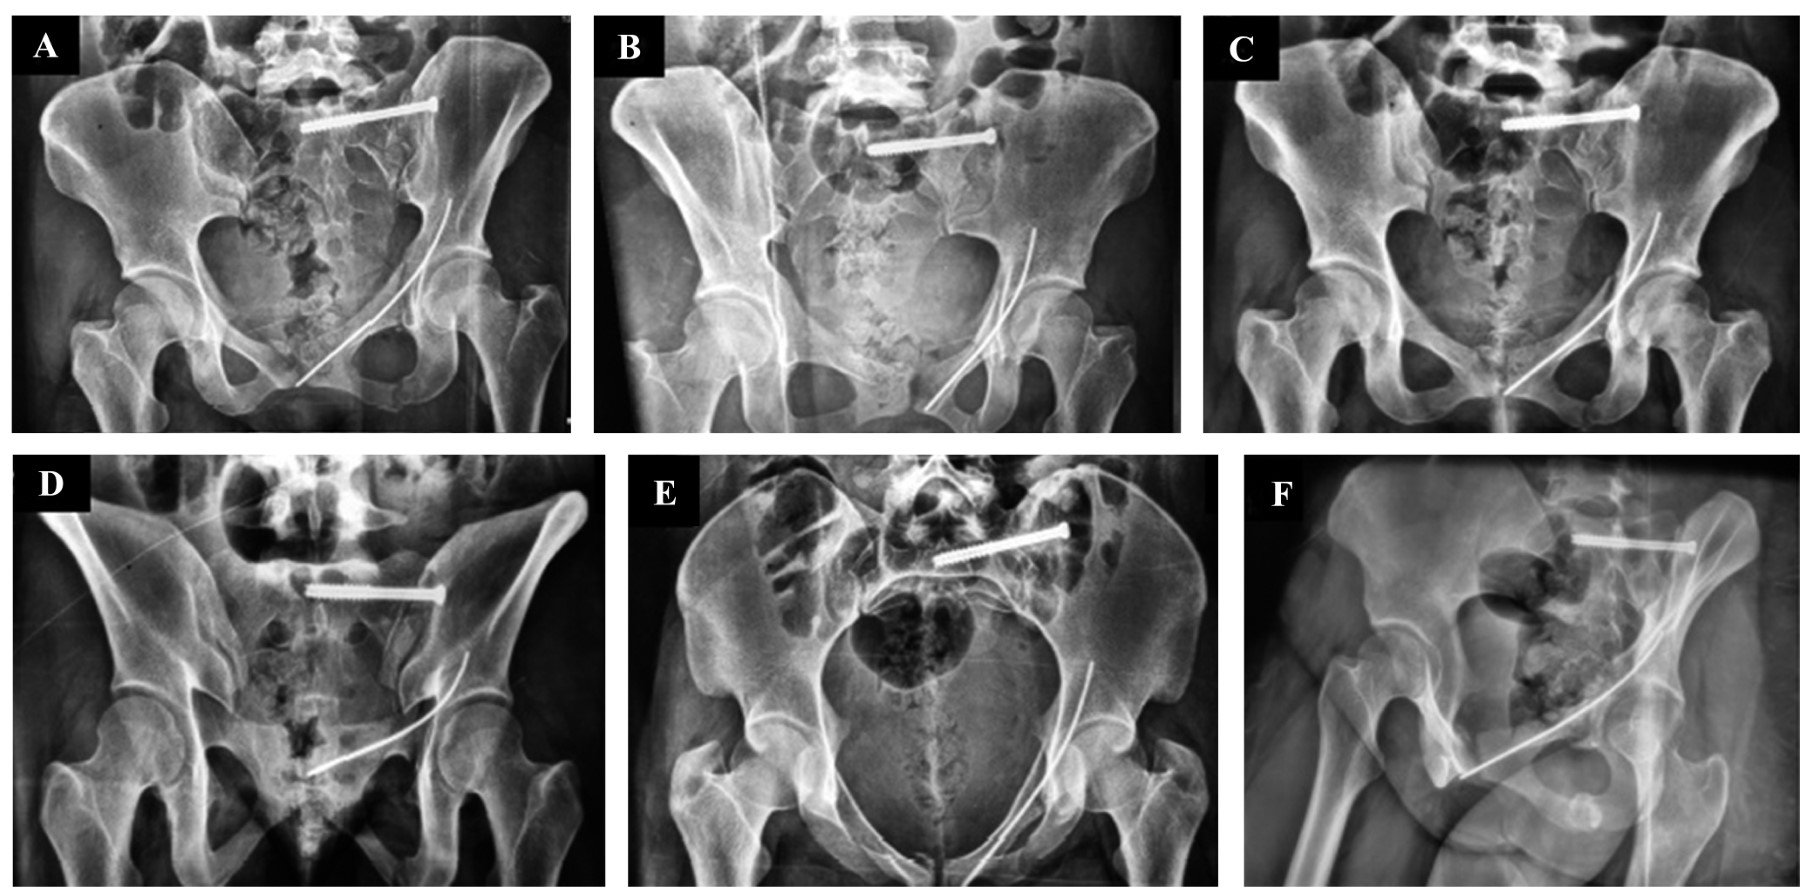

Figura 1